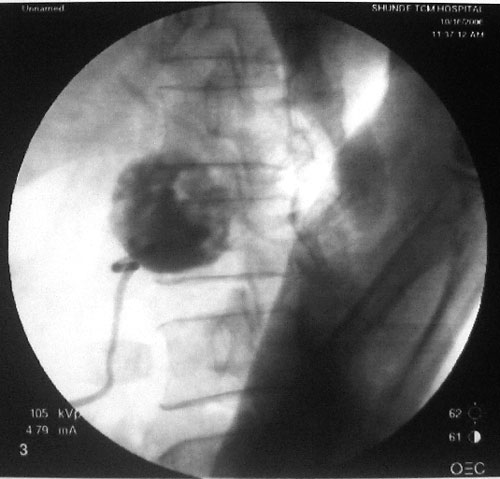

参照ct片,经皮穿刺,抽出透明液体60ml,随后置入引流管引流,囊液细胞学检查阴性,胰酶检查阴性。采用无水乙醇灌注治疗。4天后囊腔闭锁,无液体渗出,予以拔管。

置管后造影,显示囊腔直径约5cm,囊壁光整,正位、双斜位造影均未见造影剂外溢,与胰腺无交通